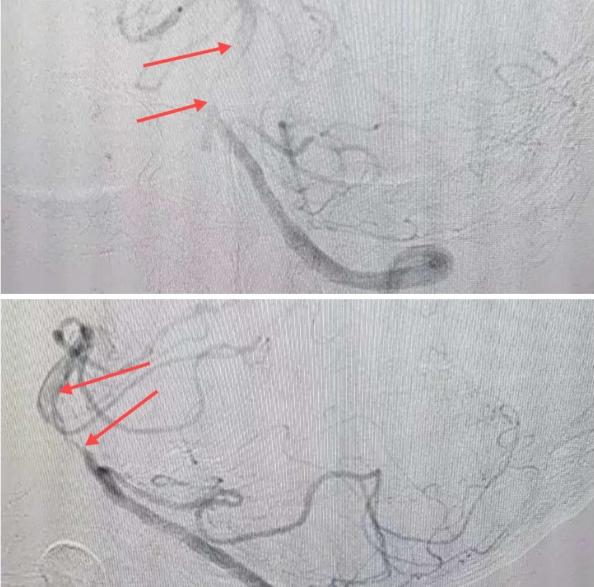

在經(jīng)造影后,主刀醫(yī)生腦一科副主任楊慶堂發(fā)現(xiàn)患者基底動(dòng)脈下段重度狹窄且狹窄段以遠(yuǎn)有大負(fù)荷血栓,其狹窄處考慮為動(dòng)脈夾層,手術(shù)難度及風(fēng)險(xiǎn)較大。楊慶堂副主任在彭壯副主任醫(yī)師的協(xié)助下運(yùn)用spaceman(太空人)技術(shù),中間導(dǎo)管抵近血栓抽吸配合支架拉栓,成功開通血管。再次造影可見基底動(dòng)脈管腔明顯增寬,遠(yuǎn)端血管顯影良好,且等待20分鐘后造影仍顯示血流通暢。楊慶堂副主任考慮到本次手術(shù)時(shí)間不宜過長,現(xiàn)患者基底動(dòng)脈及分支前向血流維持良好,給予其抗栓藥物應(yīng)用后結(jié)束手術(shù),并建議患者3個(gè)月后復(fù)查造影,明確其基底動(dòng)脈夾層情況。

造影可見血管夾層和大量血栓形成

取栓后血管管腔增寬,前向血流良好